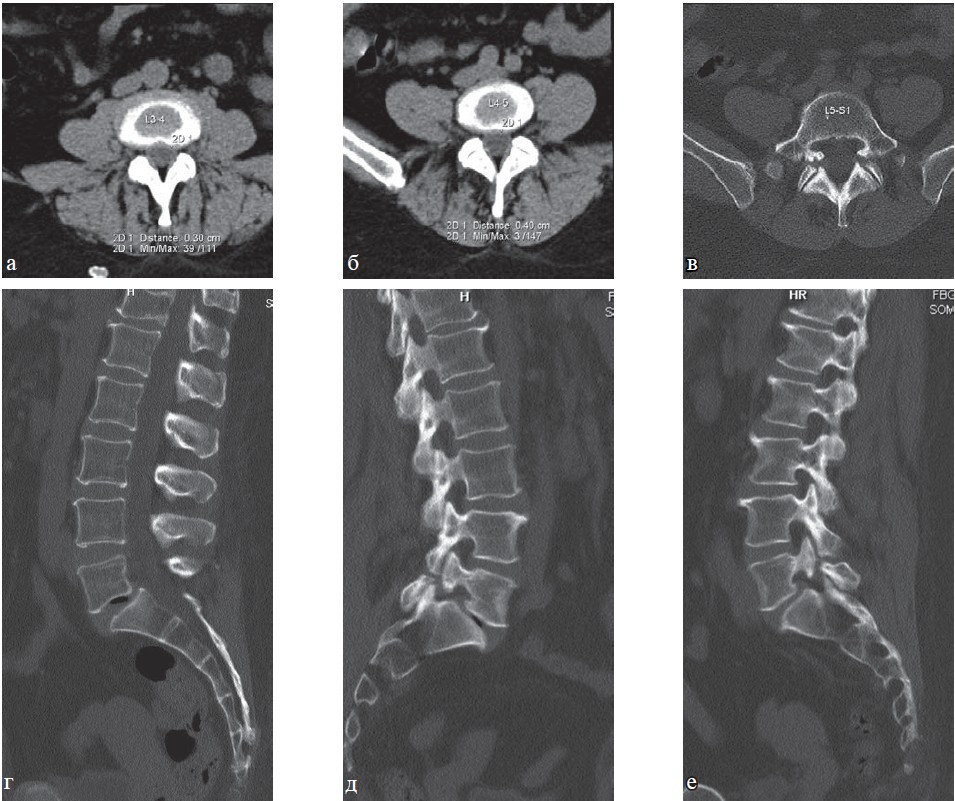

В 3-ю группу были отнесены 83 пациента, у которых выявлены остеохондроз позвоночника III-IV стадии с выраженной дегенерацией диска и его пролапсом более 7 мм, секвестрацией, с выраженными явлениями спондилоартроза и гипертрофией желтых связок (стеноз позвоночного канала, сужение корешковых отверстий), нарушением плотности и структуры кости (остеопороз), спондилолистез II-III степени, болезнь Бехтерева (рис. 7-10).

Рис. 10. МРТ поясничного отдела позвоночника в сагиттальной плоскости. Больная Д., 58 лет: а — Т1-ВИ, б — Т2-ВИ, в — МР-миелография. Остеохондроз пояснично-крестцового отдела позвоночника IV степени, протрузии межпозвонковых дисков Th12-L1, L1-L2, L2-L3. Грыжи межпозвонковых дисков L3-L4, L4-L5. Деформирующий спондилез, спондилоартроз, передний спондилолистез L2 I ст. Узкий дегенеративный позвоночный канал.

По данным МРТ выявлены изменения межпозвоночных дисков и позвоночного канала, требующие санаторно-курортного лечения в щадящем режиме.

Физическая работоспособность больных 3-й группы резко снижена или минимальна. Переносимость лечебных факторов и физической нагрузки позволяет назначить им лишь щадящий режим санаторно-курортного лечения с минимальной степенью воздействия и интенсивности.